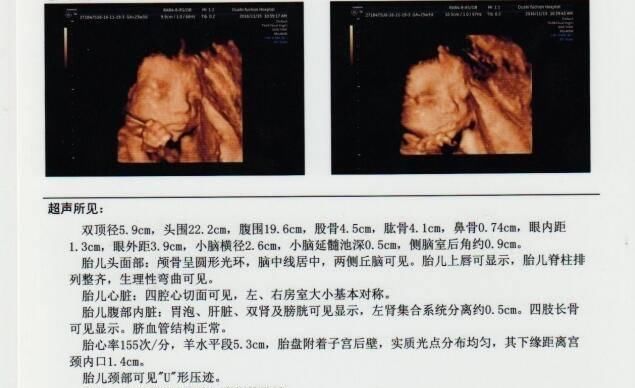

其实对孕妈来说,检查报告最不明确的应该是各个数据的意义,比如图示的双顶径5.9cm,这个双顶径是什么?5.9cm标准吗?对胎儿有哪些影响呢?所以说,只要明确了几个重要数据的意义,那检查报告对孕妈来说,看起来就会很容易了。

如图示,羊水平段5.3cm。这个羊水平段,也就是羊水深度,是指B超检查的最大羊水池的垂直深度,正常范围为3-8cm,小于3cm羊水过少,大于8cm羊水过多,过多多少都得重视。

胎心率也是每次B超检查必须的,对胎儿来说非常重要,胎心率正常值为120-160次/分钟,如果低于120次/分钟,或者高于160次/分钟,都代表胎儿宫内异常,可能有缺氧危险。